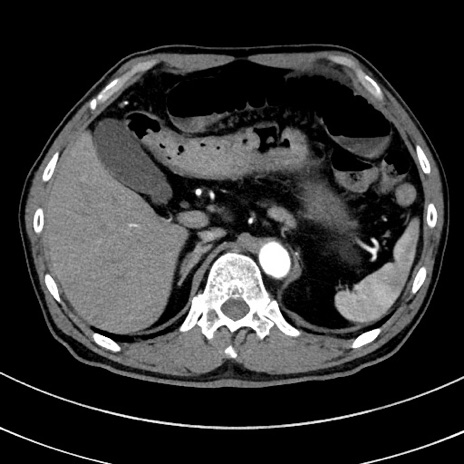

症例8(横断像)

【症例】 60歳代男性

【主訴】 黒色吐物

【現病歴】 4日前から嘔気自覚、2日前の朝食後にも嘔気あり、自分で手で嘔吐反射起こし嘔吐したところ血が混ざっていたため受診。

【既往歴】 5年前汎発性腹膜炎を伴う急性虫垂炎で手術、高血圧、前立腺肥大症、高脂血症

【身体所見】 腹部正中に手術癩痕あり 腹部平坦・軟圧痛なし膨満感あり

【データ】WBC 8400、CRP 4.54